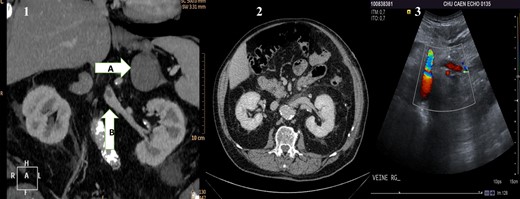

(1) Preoperative CT scan showing the adrenal mass (A) and in the renal vein a hypodense mass (B) corresponding to the renal vein tumor thrombus. (2) Postoperative CT scan showing the left kidney and its permeable vein. (3) Flow in the left renal vein on postoperative Doppler ultrasound.

A 74-year-old man was referred in December 2011 to our hospital for an adrenal mass, discovered during the follow-up of a pT3-N1 M0 large cells neuroendocrine lung carcinoma, treated in June 2011 by surgery. The lobectomy had been followed by four adjuvant cures of carboplatin GP 16. His main past medical history was hypertensive cardiopathy and non-insulin-dependent diabetes mellitus. On a clinical point of view, he had no symptoms and in particular no general physical deterioration. The computed tomography (CT) scan showed a left adrenal mass (7 × 10 cm enhanced with contrast) associated with a renal vein tumor thrombus (Fig. 1). A positron emission tomography scanner showed adrenal mass and renal vein tumor thrombus hypermetabolism proving their tumoral hallmarks. Surgical treatment was decided after anticoagulation treatment initiated (continuous intravenous administration of sodic heparin at the dose of 500 international unit/kg/day); after a left subcostal incision, the left colon was mobilized and the retroperitoneal space approached. Once the adrenal gland was visualized, its main vein was isolated and followed until the renal vein to localize the tumor thrombus. Using kidney cancer surgical technique for vena cava thrombectomy, we isolated all the confluents to the renal vein. After quadruple clamping (renal vein X2, spermatic vein and lumbar vein), the left renal vein was laterally opened in order to perform the thrombectomy, and the main adrenal vein was cut. Total clamping time was 12 min with no arterial clamping and no renal cooling required. The renal vein was washed with a heparinized saline solution and closed with a polypropylene 6/0 running suture. Then, the veins were unclamped, and finally the adrenal gland was removed with macroscopically disease-free margins taking away the adrenal fat along the upper renal pole capsule.

The postoperative management was simple except for an Aeromonas hydrophila pulmonary infection, which was successfully treated by a 15-day cure of antibiotics. The patient was discharged on Day 15. Histopathological studies revealed a 7-cm ‘round’ cells undifferentiated tumor with a vein tumor thrombus. No adjuvant treatment was proposed because there was no relation with the lung carcinoma, and tumor's resection margins were negative. The postoperative CT scan showed no thrombus in the left renal vein (Fig. 1). Doppler ultrasound performed 1 month after adrenalectomy proved a good left renal vein flux (Fig. 1). At 36 months of follow-up, the patient is alive without signs of recurrence.